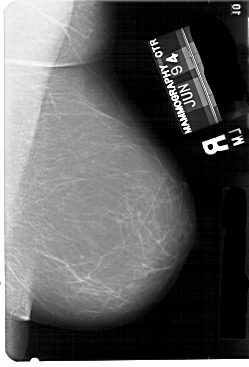

A_1437_1.LEFT_MLO

LEFT_MLO LINES 5491 PIXELS_PER_LINE 3496 BITS_PER_PIXEL 12 RESOLUTION 43.5 OVERLAY

FILE: A_1437_1.LEFT_MLO.OVERLAY

TOTAL_ABNORMALITIES 1

ABNORMALITY 1

LESION_TYPE MASS SHAPE IRREGULAR MARGINS ILL_DEFINED

ASSESSMENT 3

SUBTLETY 2

PATHOLOGY BENIGN

TOTAL_OUTLINES 1

BOUNDARY